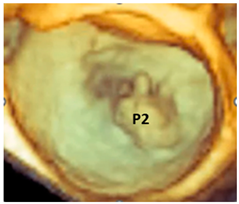

| Fibroelastic deficiency | This phenotype is characterized by a deficient production of collagen, elastin, and proteoglycans. Leaflets preserve their own three-layer arrangement, but upon surgical inspection, they appear fragile and translucent. The etiology of connective tissue deficiency in FED is unknown, but it has been suggested that it may be the result of an accelerated ageing process. The cause of regurgitation is the rupture of one or more primary chordae tendineae, which usually involves a single scallop. The figure shows a small P2 prolapse in an otherwise apparently normal MV. |  |